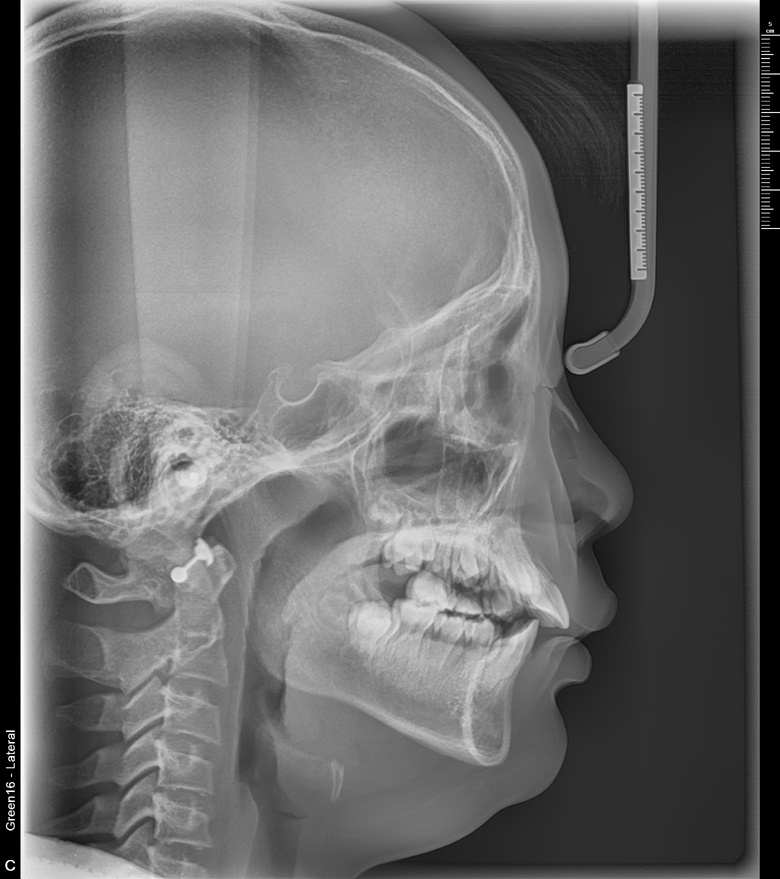

치료 후 사진입니다.